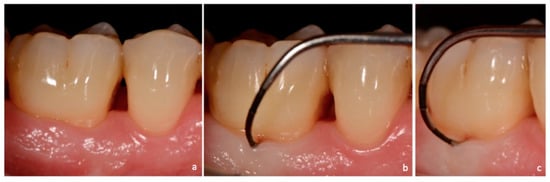

Figure 2. Non-exposed furcation lesion—Class I (NEI): (a) First maxillary molar; (b) Buccal furcation lesion. Horizontal attachment loss of 2 mm.

Class I: incipient lesion. There is slightly horizontal attachment loss in the furcation area. The examiner probe penetrates two millimeters or less from the entrance of furcation (Figure 2, Figure 3 and Figure 7).